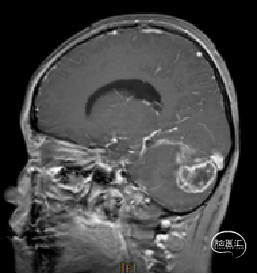

现病史:患者18个月前无明显诱因出现间断头痛,休息后可缓解,开始未予重视,未行特殊治疗。1周前患者无明显诱因出现恶心、呕吐,就诊于当地医院,行颅脑MRI提示:小脑囊实性占位性病变,首先考虑毛细胞星型细胞瘤。现患者为求进一步治疗就诊于我院,门诊以“脑肿瘤”收入院。患者自发病以来神志清,精神可,饮食睡眠正常,二便如常,体重未见明显下降。

术前MRI